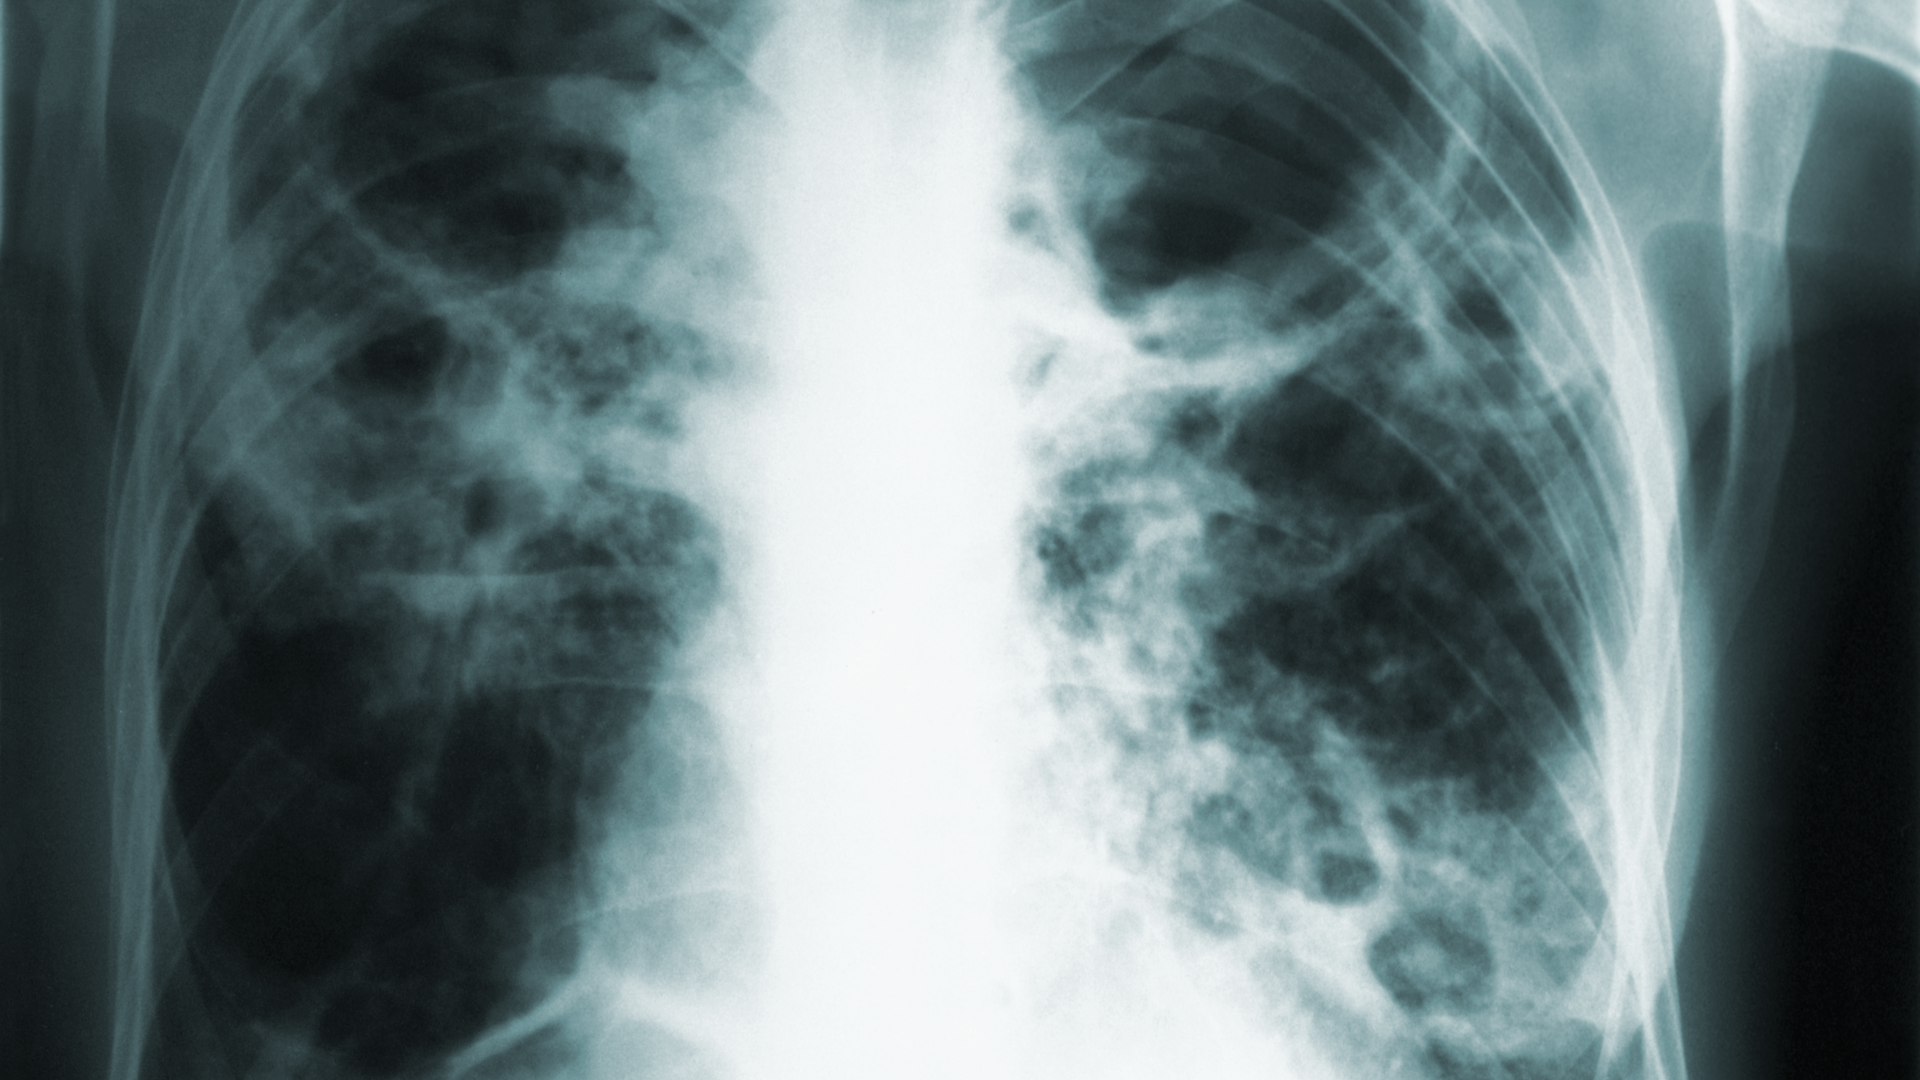

COVID’s impact on TB

According to a release by the Centers for Disease Control and Prevention (CDC), in the United States, reported tuberculosis (TB) disease diagnoses fell 20% in 2020 and remained 13% lower in 2021 than TB disease diagnoses made prior to the COVID-19 pandemic, according to CDC data.

The new data suggest that the pandemic has had a substantial effect on TB trends in the United States. Before COVID-19, TB disease diagnoses typically declined between 1% and 2% each year. The 2020 and 2021 declines may be related to factors associated with the COVID-19 pandemic, including a true reduction in incidence as well as delayed or missed TB diagnoses. For example: